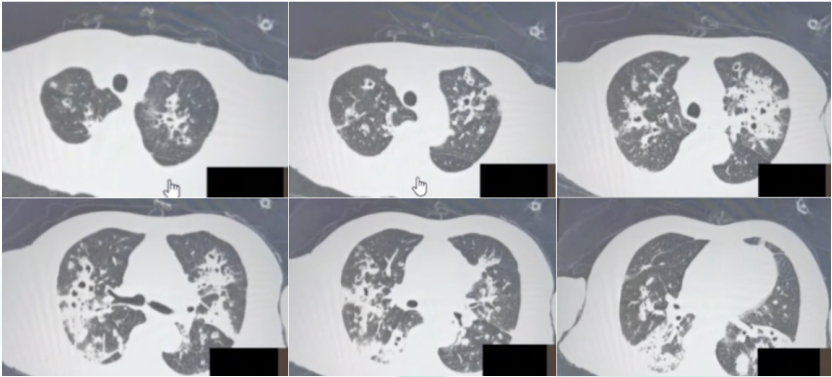

5月8日复查胸部CT可见空洞样病变较前有所吸收; 6月9日复查病灶进一步吸收10月9日随访胸部CT见病灶基本完全吸收(图15)

15  患者病程中胸部CT对比